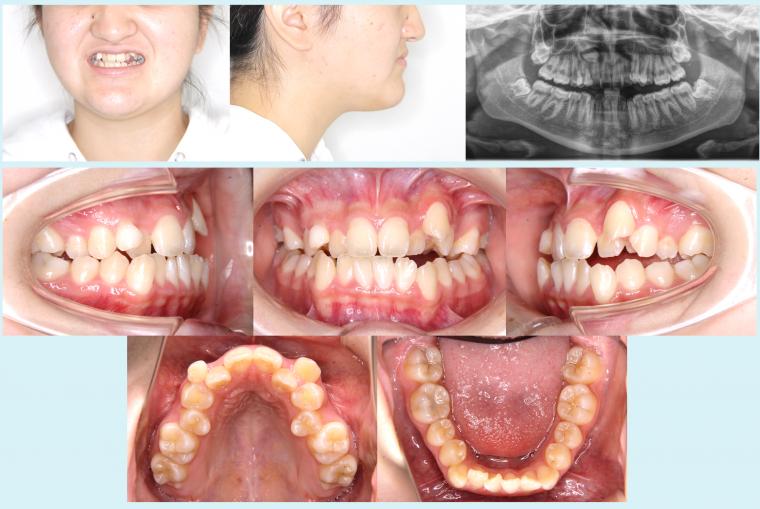

#44 上顎歯列の狭窄を伴う叢生症例